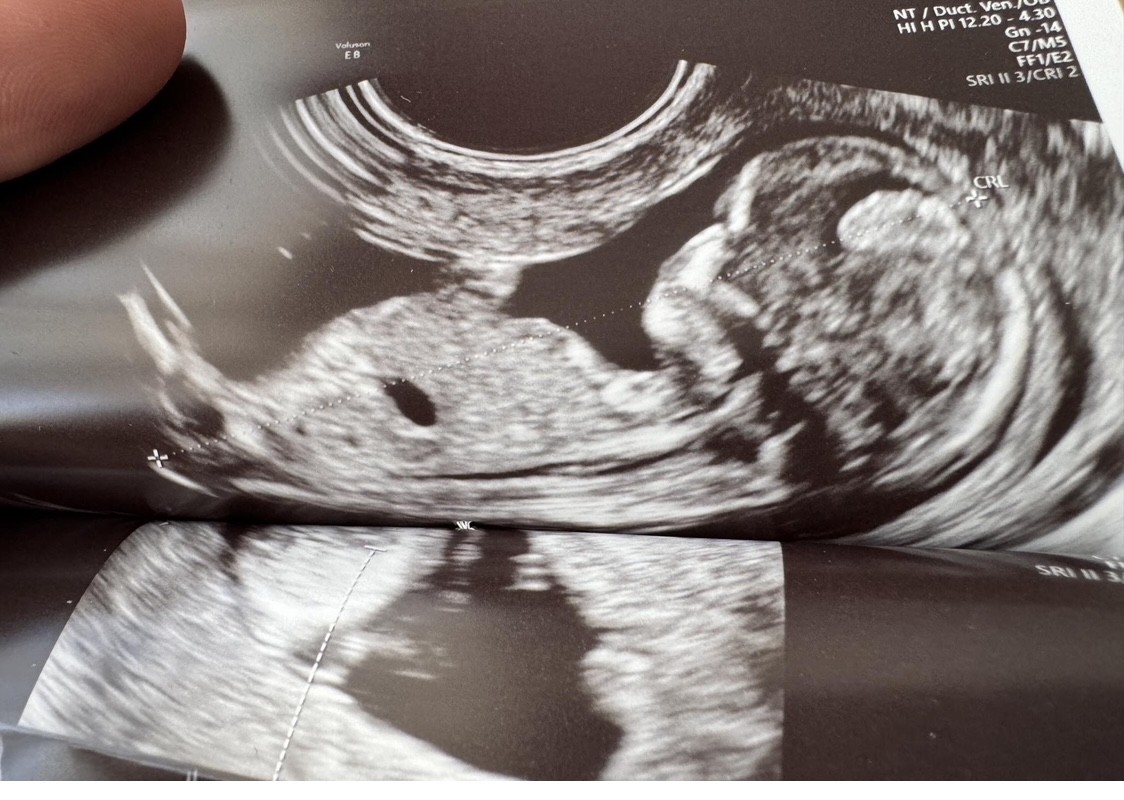

Zaczynam właśnie 7 miesiąc ciazy, czas kompletować wyprawkę :) na 1 prenatalnych i wizytach lekarskich do 19 tyg chłopak, widziałam siusiaka, w 20 tyg na 70% dziewczynka, później już nic nie było widać… ostatnie USG, ułożenie miednicowe, pępowina między nogami :p czy na tych zdjęciach da się coś rozpoznać względem wyrostka? :)

• IMG_7106.jpeg

IMG_7106.jpeg

199,7 KB · Wyświetleń: 78

• IMG_7107.jpeg

IMG_7107.jpeg

169,4 KB · Wyświetleń: 76